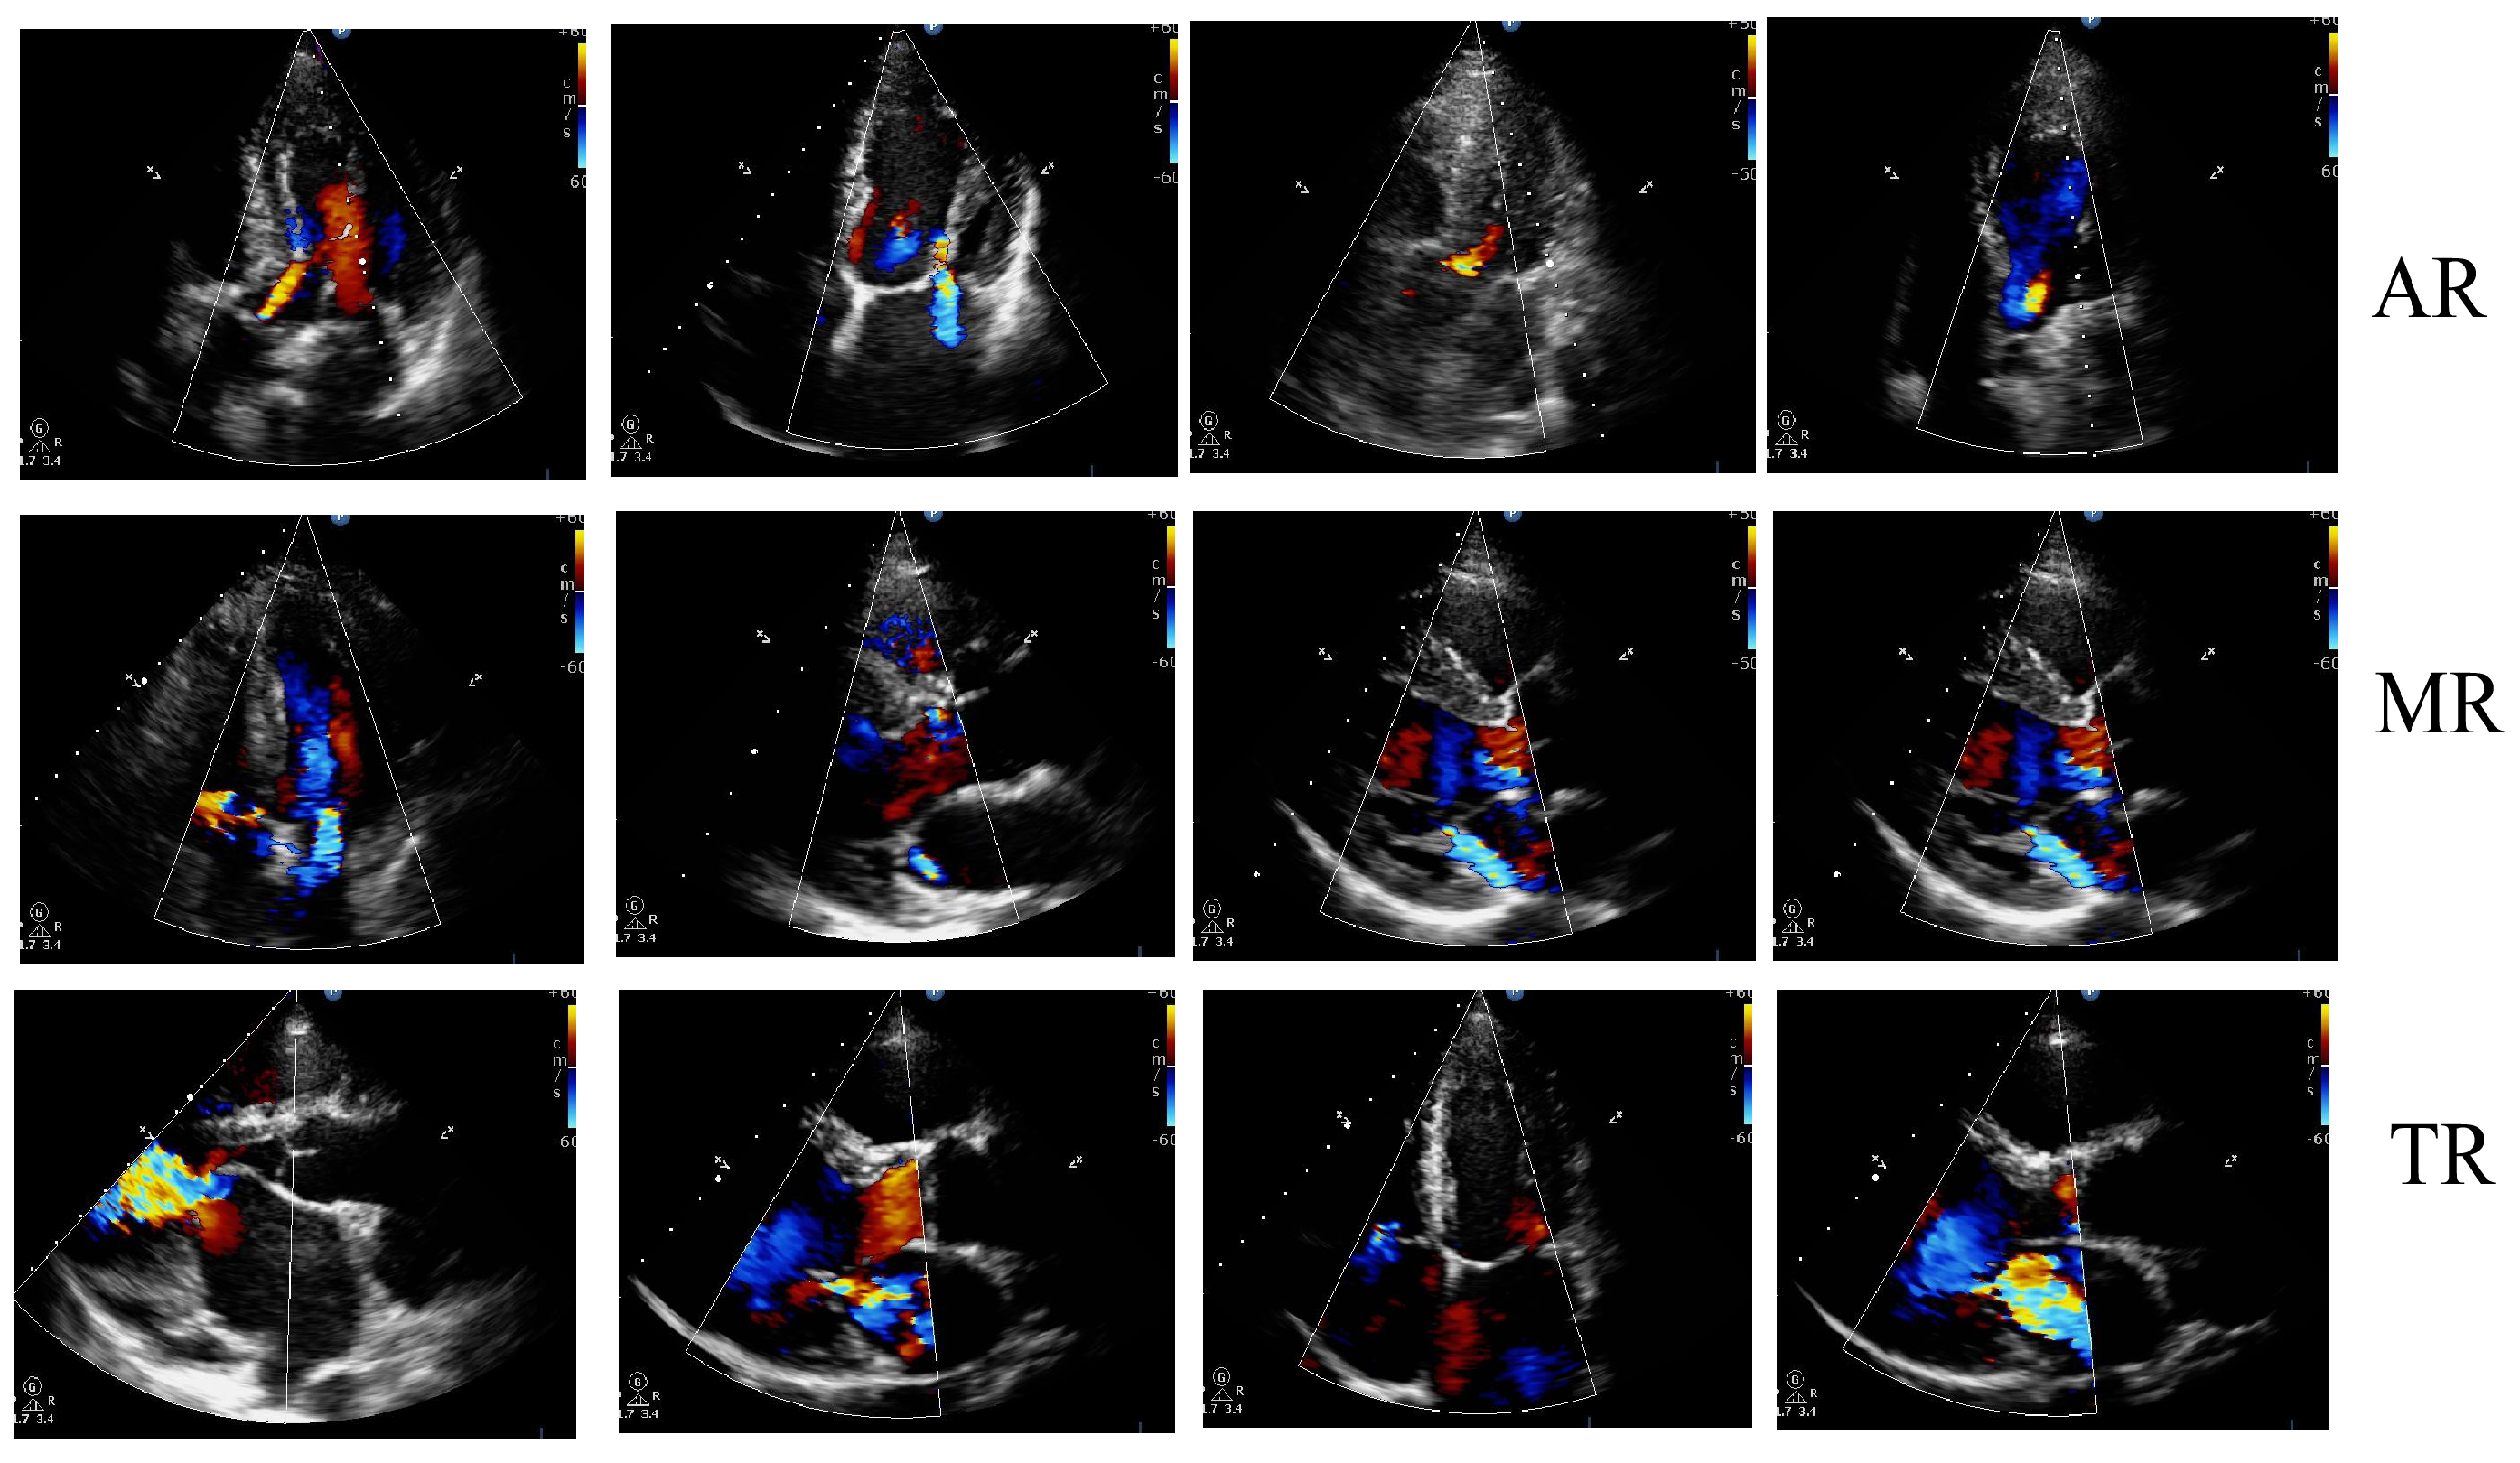

4.2. Dataset

4.3.1. Preprocessing and Segmentation Output